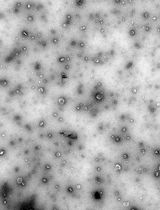

Every year, there is an increase in the number of cases of chronic kidney disease, and a delay in the initiation of adequate treatment can lead to kidney failure, which requires regular dialysis or transplantation. Intensive systemic therapy used to treat kidney diseases often has a negative impact on other weakened organs, making it crucial to ensure targeted delivery of medications directly to the kidneys and to minimize systemic side effects. In order to reduce the toxicity of medications and decrease dosages, innovative delivery methods are being developed, such as micro-sized targeted delivery systems, which ensure highly effective distribution of encapsulated drugs directly within the organs. In a recent article, we presented innovative emulsified microgels stabilized with whey protein isolate (WPI), specifically designed for targeted drug delivery to the kidneys. Our stability studies revealed that these microgels start to degrade after 72 h, with this degradation exhibiting a time-dependent profile. Furthermore, intravenous administration of the microgel suspension through the tail vein showed significant selective accumulation in both the liver and kidneys over a duration of 5 days. As part of our research, we present the protocol for synthesizing emulsion microgels derived from whey protein isolate. This article provides a comprehensive overview of the procedures for precursor preparation, along with an in-depth investigation of the emulsion system's stability over time. The protocol also includes the injection of an emulsion microgel suspension into the tail vein of mice, enabling the evaluation of their biocompatibility and potential therapeutic efficacy. This protocol outlines the precautions and important nuances that should be considered at each stage of the experiment.

Due to the possibility of varying the synthesis conditions to produce microgels with precisely specified physical and chemical properties, such as particle size, surface area, zeta potential, and drug loading efficiency, emulsion microgels have been studied as a potential drug delivery system for the kidneys [11]. Intravenous delivery of these microgels resulted in a long-term accumulation (at least 5 days) of these particles in the liver and kidneys, indicating a high efficiency of biodistribution and targeting to the target organ. The experimental conditions for synthesizing these microgels allow for the creation of particles with exactly the desired characteristics. The developed microgels provide a customized therapeutic approach to the treatment of kidney diseases, with reduced side effects. This opens up new possibilities for the systemic treatment of the urinary system.